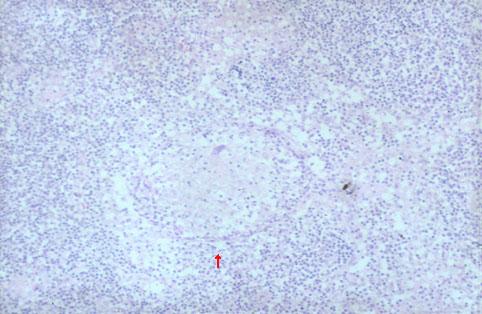

직장의 누공형성을 동반한 소장 크론병의 절제례

[Image-ID:2789]

염증성 및 궤양성질환/크론병

소장/공장

마이크로